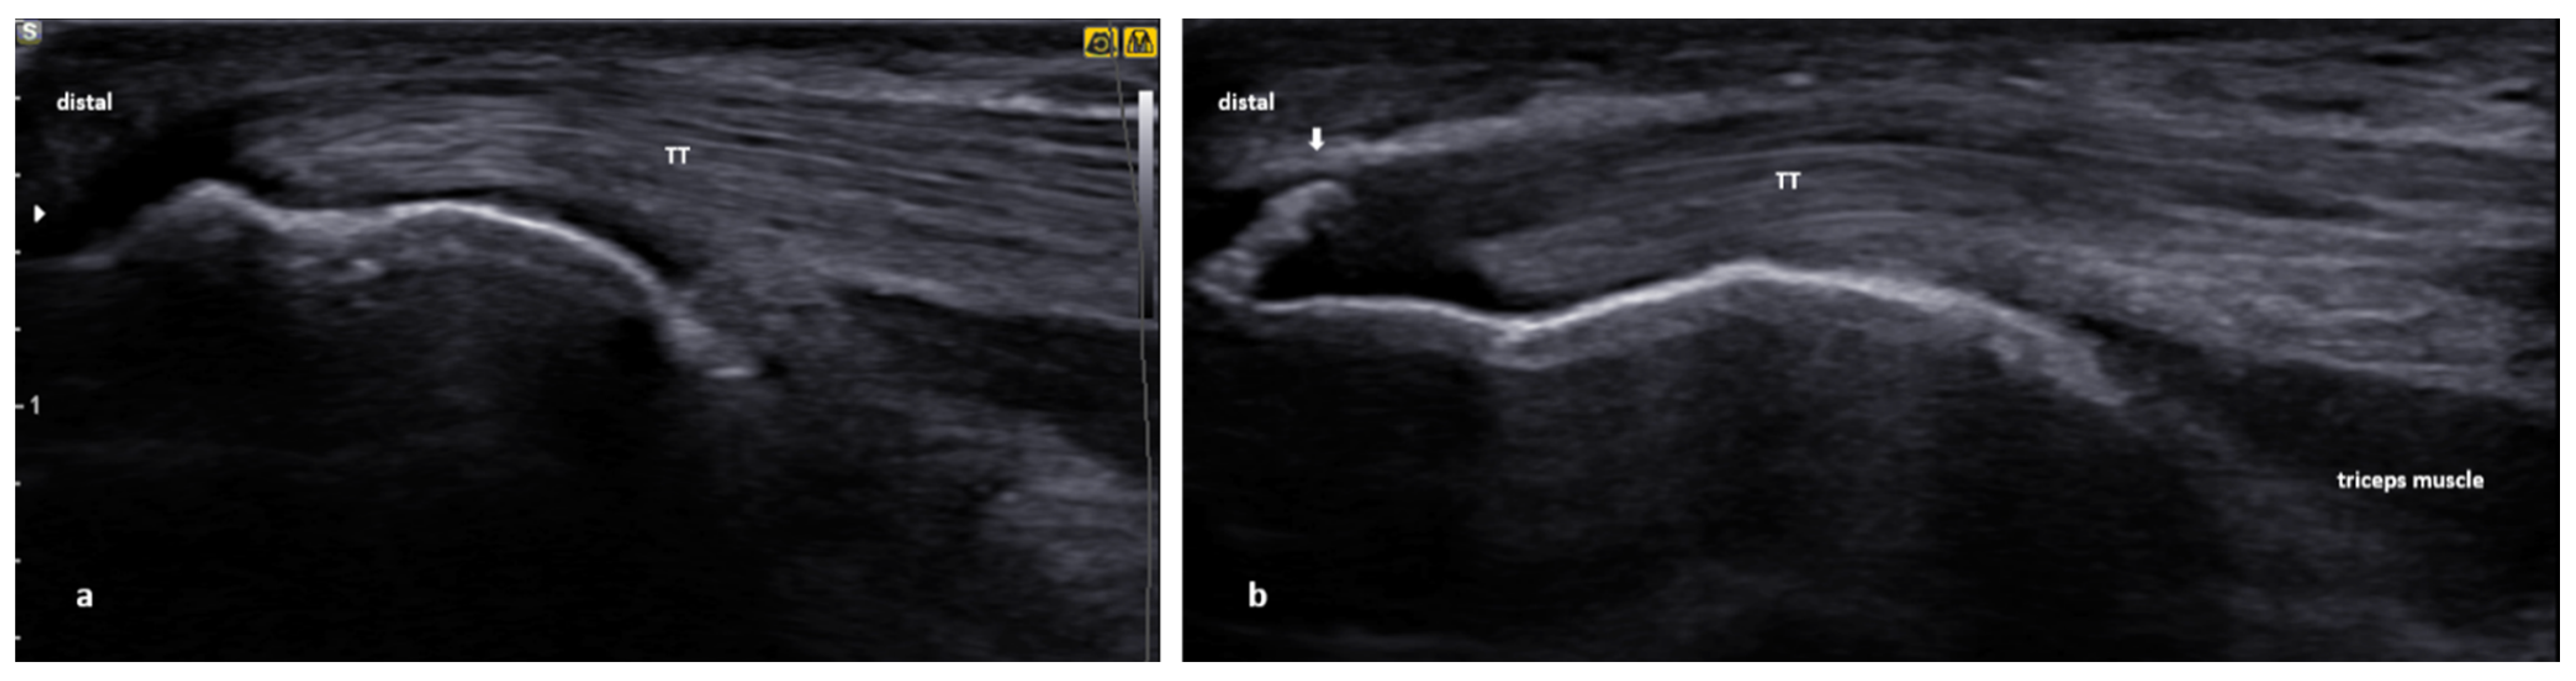

3.3. Distal Biceps Tendinopathy

3.3.2. US Scanning and Guided Injection